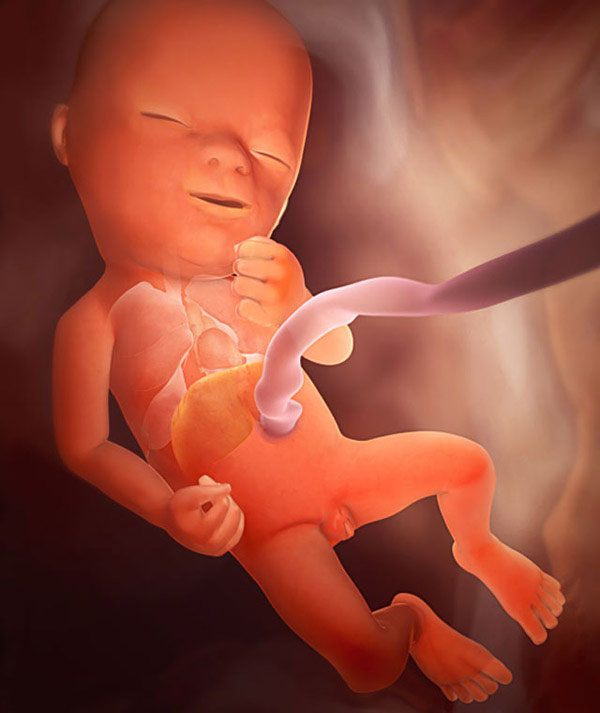

Kūdikio nuotrauka (taip vaisius atrodo penkioliktą nėštumo savaitę):

kūdikis-15 savaičių nėštumas

15-nedel-plod

Mažas vaikas aktyviai „treniruojasi“, judina rankas, kojas ir pirštus. Šiuos judesius kontroliuoja smegenų motoriniai refleksai. Kūdikis gali išgirsti aplinkinius garsus. Maža širdis kasdien pumpuoja virš dvidešimt litrų kraujo.